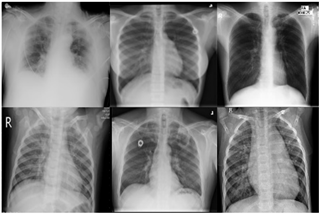

The total dataset contains 6,000 datasets which were divided into 6 classes. Each class in the dataset contains 1,000 data samples. The data samples in each class were split in the proportion of 80:20 to train and test, while 10 percent of the training samples were used for validation to prevent overfitting. Table 1 illustrates the distribution of the dataset. Figure 1 depicts the images of chest X-rays of viral pneumonia, COVID-19, normal, tuberculosis, lung opacity, and bacterial pneumonia.

Figure 1. Included in the sample images of chest X-ray used in this study (a) COVID 19; (b) Pneumonia; (c) Normal; (d) Tuberculosis positive; (e) lung-opacity; (f) bacterial pneumonia